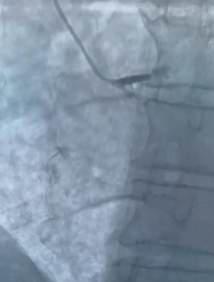

Sin duda el procedimiento más común que se realiza es el diagnóstico y tratamiento de infarto al corazón, con colocación de “stent coronario”.

Un paciente de 70 años aproximadamente, el cual llegó con la presencia de infarto al corazón y se identificó la presencia de oclusión total del tronco coronario izquierdo, que es de donde salen dos de las principales arterias del corazón. Afortunadamente, se pudo liberar la obstrucción con colocación de dos stent y el paciente está al momento estable, realizando su vida de manera normal.

El infarto sucede por una obstrucción critica de los conductos coronarios que llevan sangre al corazón, esta obstrucción sucede al acumularse coágulos y grasas dentro de las coronarias. Mediante cateterismo cardiaco de urgencia se puede aliviar la obstrucción y mediante el “stent coronario” se puede mantener el conducto coronario abierto y llevando sangre al corazón de forma permanente.

El cateterismo cardiaco es un procedimiento mínimamente invasivo, donde mediante un piquete en la mano o en la pierna, accedemos al corazón del paciente, pudiendo detectarse y tratarse por esta vía la mayoría de las enfermedades cardiacas, ya sea angina de pecho o infartos, mediante implante de stents coronarios o enfermedades de la válvula aortica mediante el llamado TAVI (implante de válvula aórtica transcatéter).